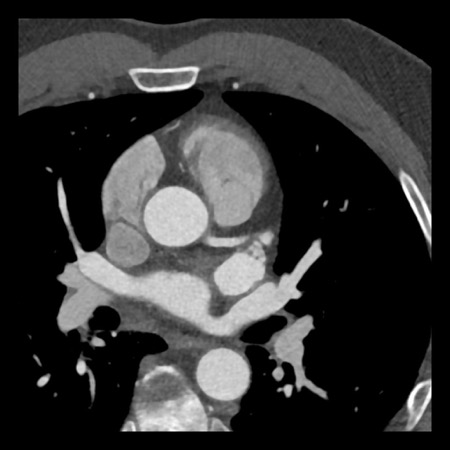

Same patient. First, study the CTA image.

How would you describe the findings?

The coronal image shows a central low-attenuation area around the lumen

of the LAD.

This low-attenuation area is surrounded by a higher attenuation

area.

This finding is the earlier discussed napkin-ring sign, which is a high-risk

plaque feature.

This patient classifies as CAD-RADS 4A/P1/HRP.